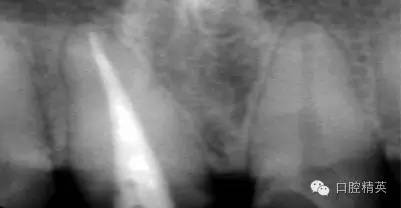

根管治療更是牙體修復(fù)的基礎(chǔ),根據(jù)術(shù)前診斷,對需要做根管治療的或有必要重新做根管治療的,一定要做到恰充,消除隱患,避免將來冠修復(fù)好后,出現(xiàn)根尖炎癥的問題(見圖3、4、5)。在基礎(chǔ)工作做好后,接下來開始牙體預(yù)備,根據(jù)跟個(gè)人習(xí)慣,選擇合適的車針(圖6、7)。